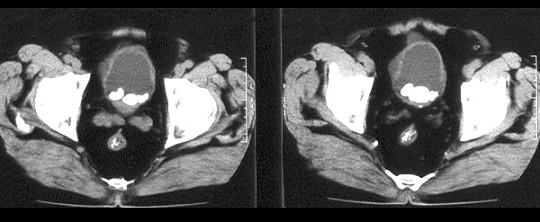

问题 男,58岁。大量无痛肉眼血尿伴血凝块1天,排尿困难1天。检查:血压120/75mmHg,脉搏82次/分,耻骨上及脐下压痛,叩诊浊音。 本患者以下诊断中哪种疾病的可能性不大 ( )

选项 A、肾盂肿瘤 B、前列腺增生症 C、肾癌 D、膀胱结石 E、膀胱肿瘤

答案 D